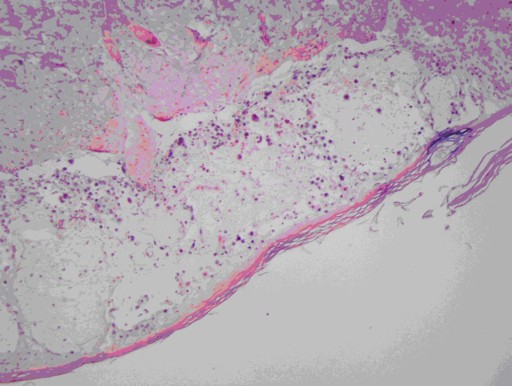

Beginning several months ago, some of the physicians of our Department of Gastroenterology noticed a general pattern of newly diagnosed autoimmune pancreatitis with recent shingles outbreak or Zoster vaccine administration. To further study the possible association, we conducted a pilot study to examine the incidence of autoimmune pancreatitis with concomitant Varicella Zoster Virus. We identified four patients from the Mayo Clinic Medical Data Trust who had undergone core biopsy or surgical resection of the pancreas and had been diagnosed with autoimmune pancreatitis. All cases of autoimmune pancreatitis were associated with an elevated (more than 1.5 x upper reference limit) IgG4 level as well as histologic changes consistent with the diagnosis. With these four cases of autoimmune pancreatitis identified, we identified two cases for controls with normal pancreatic tissue. Both of these groups of tissue samples had already been collected and were accessed from the Mayo Medical Laboratory. Once the six tissue samples were obtained, we conducted in-situ hybridization assays for Varicella Zoster Virus. We used this technique because it enables localization of the viral DNA in the tissues if present. Finally, we calculated the incidence of Varicella Zoster Virus antibodies in normal pancreatic tissue and in autoimmune pancreatitis tissue samples. Out of the four cases of confirmed autoimmune pancreatitis, zero tissue samples showed evidence of concomitant Varicella Zoster Virus on in-situ hybridization assays. Positive controls for Varicella Zoster Virus in-situ hybridization were used (Figure 1). Autoimmune pancreatitis is a disease process with many aspects which are still not well understood due to its relatively low incidence. Although we noted an anecdotal association between exposure to Varicella Zoster Virus and onset of autoimmune pancreatitis, we were unable to identify any evidence to support a link between these events. Specifically, none of our tissue samples diagnosed with autoimmune pancreatitis based on histology and elevated serum IgG4 levels had a positive in-situ hybridization assay for Varicella Zoster Virus.

Figure 1. Tissue sample of a positive control for Varicella Zoster Virus in-situ hybridization. |